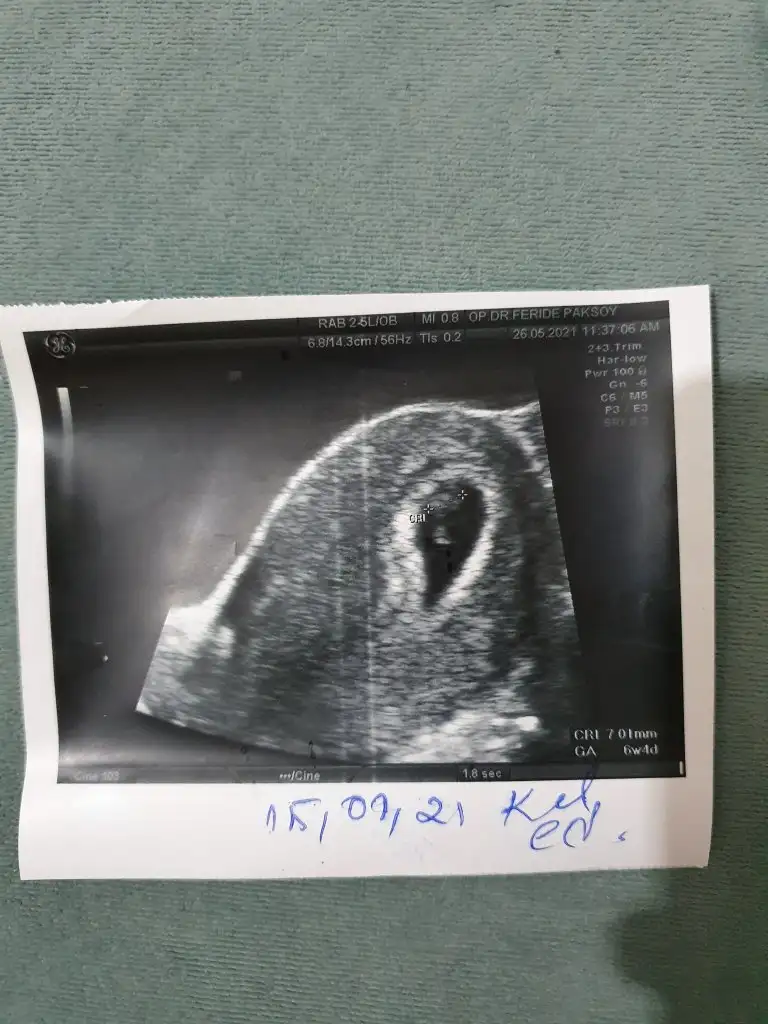

Merhaba canım 6+1haftalık daha çok küçük ama bizde bakabilir misin ? 🌸